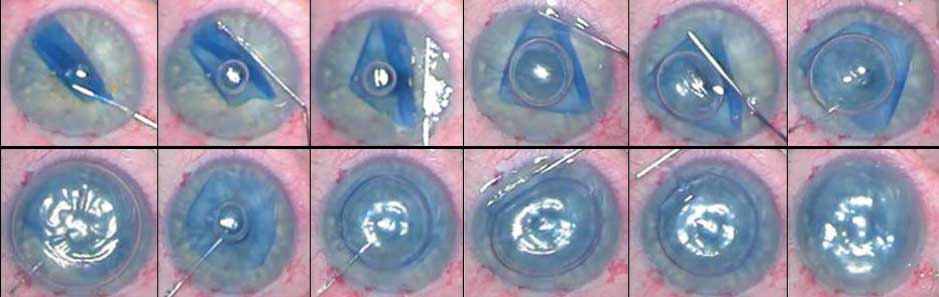

Dieser Ansatz hat den Vorteil, dass der Rest der Hornhaut intakt bleibt, was zu besseren Sehergebnissen führt. Es ist auch eine weniger invasive Technik, denn anstatt die Hornhaut vollständig zu entfernen und zu ersetzen, benötigt die lamellierende Hornhautchirurgie nur wenige kleine Schnitte, um durchgeführt zu werden, so dass auch die Genesungszeiten schneller sind. Schließlich wird das Risiko der Abstoßung erheblich reduziert. Die letzte und derzeit leistungsfähigste lamellierende Hornhautchirurgie heißt DMEK – Descemets’s Membrane Endothelial Keratoplasty, bei der die Wirtsschicht der Descemet-Membran (DM) und die Endothelzellschicht durch Spender DM und Endothel ersetzt werden. Die DMEK-Chirurgie zu erlernen ist jedoch eine besondere Herausforderung für Chirurgen.

Das ist wahr, viele Leute waren mit dem Transplantat selbst sehr unzufrieden; es war sehr schwierig, das Transplantat zu entnehmen. Das Transplantat muss wie ein Taco gefaltet werden, um durch einen kleinen Schnitt in das Auge des Empfängers eingeführt zu werden. Und dann war die Entfaltung technisch anspruchsvoll (jedes Mal, wenn Sie die Spenderhornhaut berühren, töten Sie Hornhautendothelzellen, was ein Problem darstellt). Dann müssen Sie sich unter Umständen mit postoperativen Komplikationen wie Transplantatablösungen auseinandersetzen, also waren das alles Hindernisse und Gründe, warum Hornhautchirurgen es überhaupt nicht übernommen haben. Die Menschen konnten mit Komplikationen aufwarten, die bei PKP-Volltransplantaten einfach nicht auftraten, so dass diese Chirurgen sich mit den älteren Techniken wohler fühlten. Aber auf lange Sicht sahen sie, dass die Ergebnisse der DMEK so überwältigend waren – man konnte tatsächlich visuelle Ergebnisse erzielen, die ausgezeichnet und mit der Linsenchirurgie vergleichbar waren! Und natürlich hatten wir danach einige sehr glückliche Patienten. Und wenn die Patienten glücklich sind, sind natürlich auch wir Ärzte sehr glücklich.

Das war es. Natürlich wird es jetzt einfacher. Die Operation wurde erstmals 2006 durchgeführt, so dass wir nun 13 Jahre Erfahrung haben und in diesen 13 Jahren haben wir gelernt, wie man den Graft besser handhabt. Aber in erster Linie ist es natürlich eine Herausforderung für einen Chirurgen, diesen Eingriff zum ersten Mal durchzuführen. Deshalb haben wir Kurse in Rotterdam angeboten, und ich war dort viele Jahre lang Leiterin der Akademie, wo wir Chirurgen beigebracht haben, wie man diese Hindernisse überwindet und sich besser an die DMEK-Chirurgie anpasst.

Nun, was man erwartet, ist, dass es sich um eine weniger invasive Behandlung handelt, also hat man statt der Entfernung der gesamten Hornhaut und des offenen Auges während der Operation nur minimale, kleine Schnitte, durch die man mit den Instrumenten in das Auge eindringt. Dann wird ein Graft nach Entfernung der kranken Schicht eingesetzt und mit einer Luftblase befestigt. Das ist einer der Hauptgründe, warum diese Operation so erfolgreich wurde, denn früher haben wir mit Nähten behandelt, und Nähte können dazu neigen, das Auge so zu reizen, dass das Transplantat abgestossen wird. Aber die Luftblase umgeht diese Gefahr, so dass die Patienten mit einer weniger invasiven und weniger traumatischen Operation rechnen können, und danach mit einer schnelleren Rehabilitation und einem besseren Sehergebnis. In 10 Prozent der Fälle kann sich das Graft lösen, aber nach meiner Erfahrung muss ich nur selten Luft erneut injizieren.

Was ich in den letzten Jahren gelernt habe, ist, keine Angst mehr vor den Grafts zu haben! Das ist etwas, das gerade am Anfang ziemlich beängstigend ist. Du hast Angst davor, es zu berühren, du hast Angst vor dem Graft selbst, weil es sich so verhält, wie es sich verhalten will, aber mit der Erfahrung erkennst du: „Nein, ich werde DIR sagen, was du tun musst, und Du wirst tun, was ich will“.